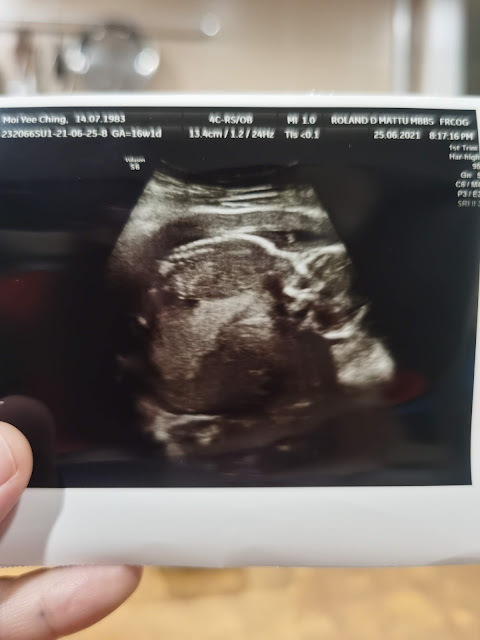

Today I am 16 weeks pregnant (around 4 months). Today went for my 3rd Pre-Natal Visit to doctor. Baby is growing healthy. At this month, I no longer feel nausea and my appetite started to getting good. I also don’t feel as tiring as before. One of the thing that we are curious about is the gender of the baby, but doctor said it’s better to confirm about it at our next visit next month.